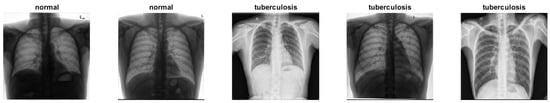

2.3. Tuberculosis Dataset